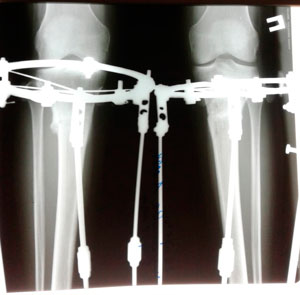

Дата снятия аппаратов- 26.07.2019г.

Срок сращения -87 дней.